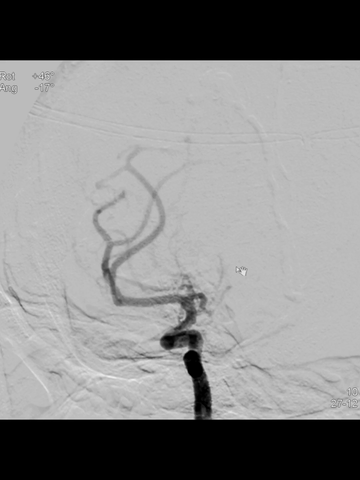

正位透视下,微导管配合,微导丝超选进入M2,侧位透视导丝符合下干走形后,微导管跟进到下干远段,造影确认位于真腔。

鉴于术前CT提示血栓范围长和负荷大,故于微导管送入一长取栓支架(4*40mm),争取一次取栓成功;支架释放后造影见:闭塞段少许前向血流,证实取栓支架已覆盖长段血栓,支架远端超出血栓远端一段较长距离。

透视下,利用支架锚定作用,将中间管头端推至ICA末端;而后中间管接50ml注射器(血管钳辅助下,保持负压状态),回撤取栓支架同时前送中间管,直至其头端达M1远端。

撤出取栓支架后,负压状态下缓慢回撤中间管,直至海绵窦段时才见回血通畅;此时见支架取栓和导管抽吸取出大量红色血栓。

海绵窦段中间管回血通畅后,造影示右ICA和MCA完全再通,前向血流良好。

放大造影示:右MCA下干近端痉挛狭窄;等待5分钟后造影见痉挛改善。

后续造影见右MCA下干痉挛明显改善;但右ACA显影不佳。